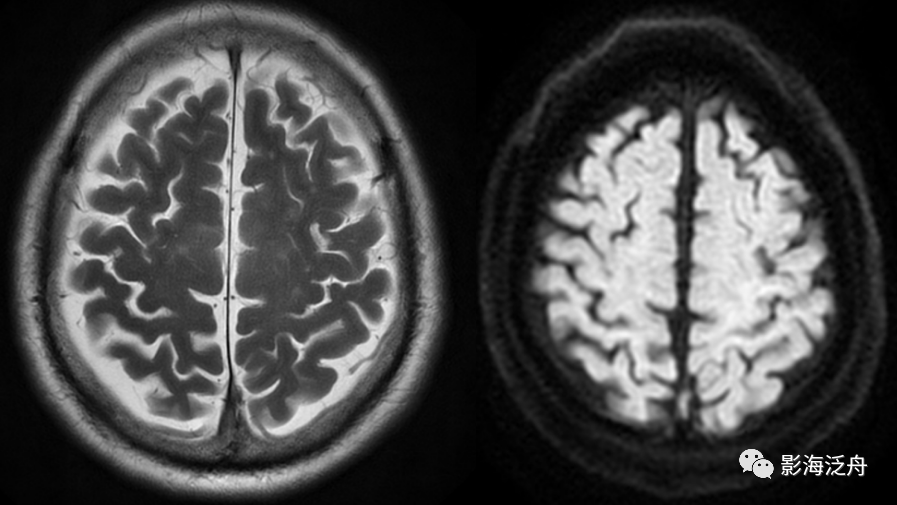

一般而言,颅脑MR平扫报告是很多刚入门的影像诊断医生喜欢写的,因为序列固定(T1WI、T2WI、FLAIR、DWI),图像加起来也就一百来张,而且通常没啥难写的,经常写的就是些缺血灶、脑白质疏松和老年脑改变,顶多来个脑出血、急性脑梗塞,遇到再难的就直接建议增强了。但事实上颅脑MR平扫也是平时工作中漏诊率最高的检查部位之一,如果不能总结教训、积累经验,长此以往恐怕会出大问题。这也是本文的目的。

今天主要和探讨一下脑血管的病变。在很多人的固有思维中,脑血管病变需要对脑血管清晰显示才能诊断,应该做CTA或DSA检查,再不济也得做个MRA或颅脑MR增强,通过MR平扫怎么能诊断脑血管病变?正是在这种想当然的定式思维下,一个个病变才得以在眼皮底下被漏掉(不怕丢人,我也漏!),不信咱们看看下面三个典型病例 ↓↓↓